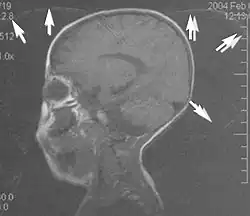

A motion artifact is one of the most common artifacts in MR imaging.[2] Motion can cause either ghost images or diffuse image noise in the phase-encoding direction. The reason for mainly affecting data sampling in the phase-encoding direction is the significant difference in the time of acquisition in the frequency- and phase-encoding directions.[1] Frequency-encoding sampling in all the rows of the matrix (128, 256 or 512) takes place during a single echo (milliseconds). Phase-encoded sampling takes several seconds, or even minutes, owing to the collection of all the k-space lines to enable Fourier analysis. Major physiological movements are of millisecond to seconds duration and thus too slow to affect frequency-encoded sampling, but they have a pronounced effect in the phase-encoding direction. Periodic movements such as cardiac movement and blood vessel or CSF pulsation cause ghost images, while non-periodic movement causes diffuse image noise (Fig. 1). Ghost image intensity increases with amplitude of movement and the signal intensity from the moving tissue. Several methods can be used to reduce motion artifacts, including patient immobilisation, cardiac and respiratory gating, signal suppression of the tissue causing the artifact, choosing the shorter dimension of the matrix as the phase-encoding direction, view-ordering or phase-reordering methods and swapping phase and frequency-encoding directions to move the artifact out of the field of interest.[1]